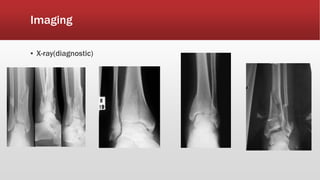

Imaging

▪ X-ray(diagnostic)